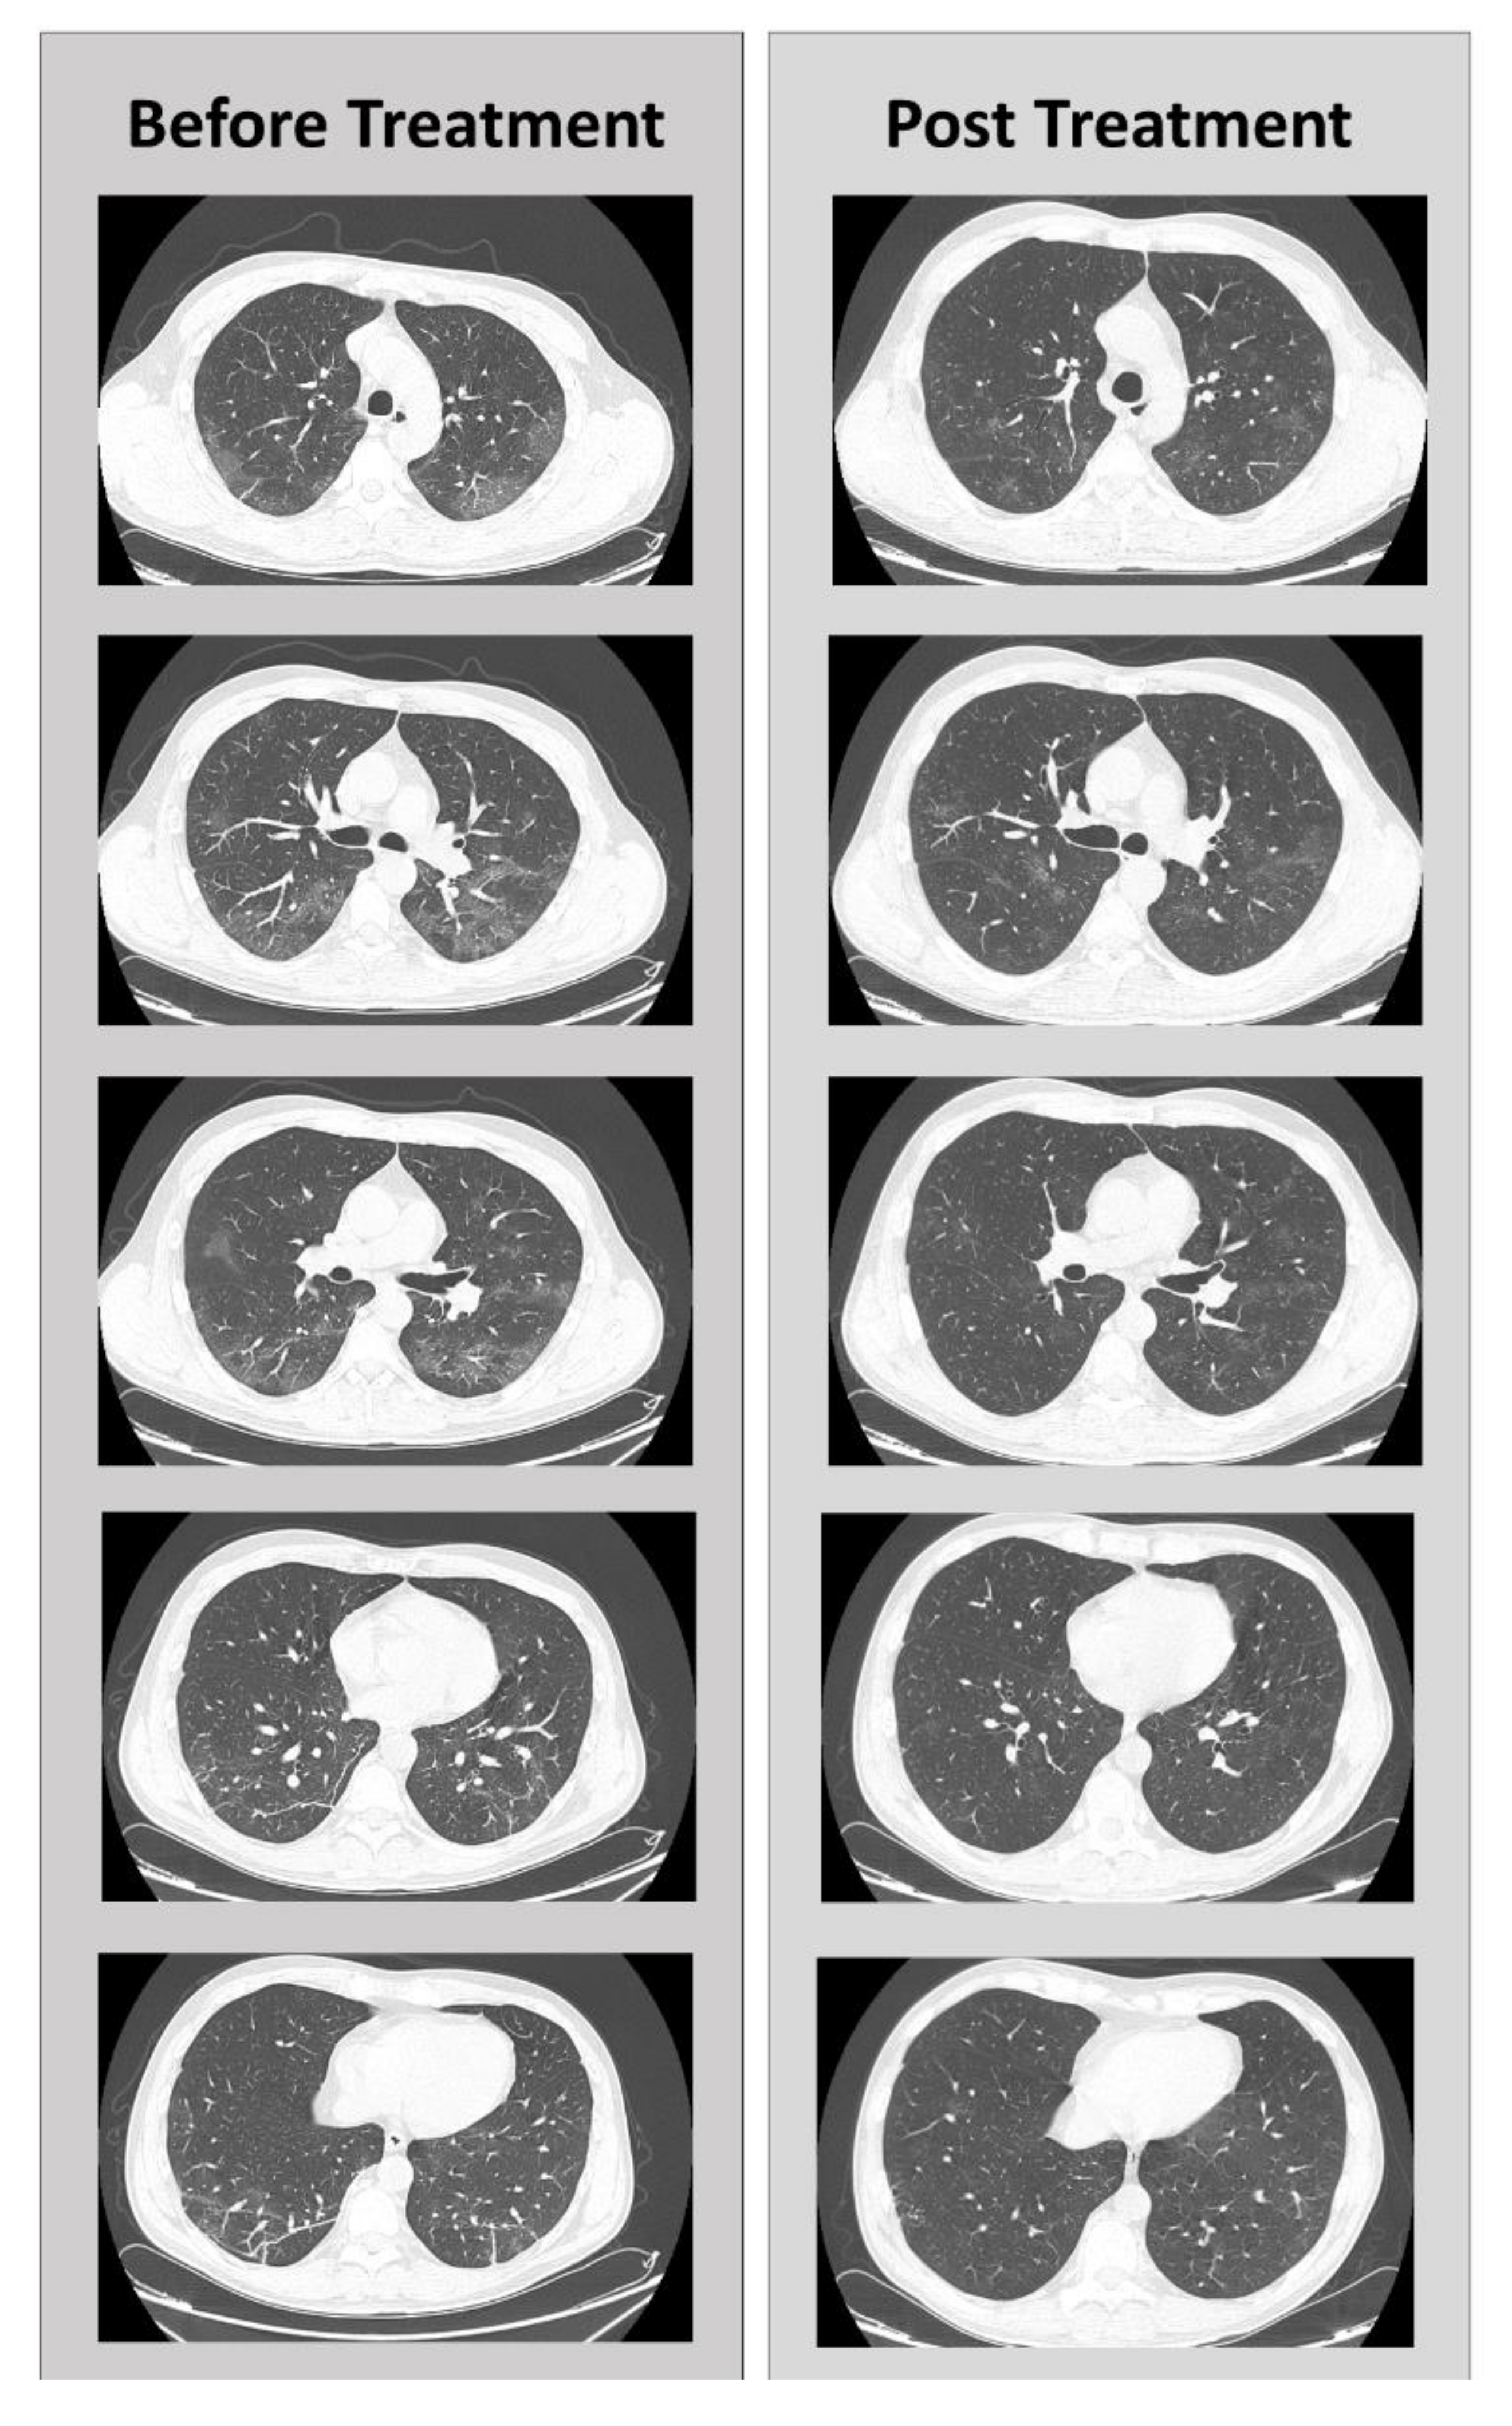

5. Clinical Case

- Caracciolo, M.; Macheda, S.; Labate, D.; Tescione, M.; La Scala, S.; Vadalà, E.; Squillaci, R.; D’Aleo, F.; Morabito, A.; Garreffa, C.; et al. Case Report: Canakinumab for the Treatment of a Patient With COVID-19 Acute Respiratory Distress Syndrome. Front. Immunol. 2020, 11, 11. [Google Scholar] [CrossRef]

- Correale, P.; Caracciolo, M.; Bilotta, F.; Conte, M.; Cuzzola, M.; Falcone, C.; Mangano, C.; Falzea, A.C.; Iuliano, E.; Morabito, A.; et al. Therapeutic effects of Adenosine in high flow 21% oxygen aereosol in patients with Covid19-Pneumonia. PLoS ONE 2020, in press. [Google Scholar]